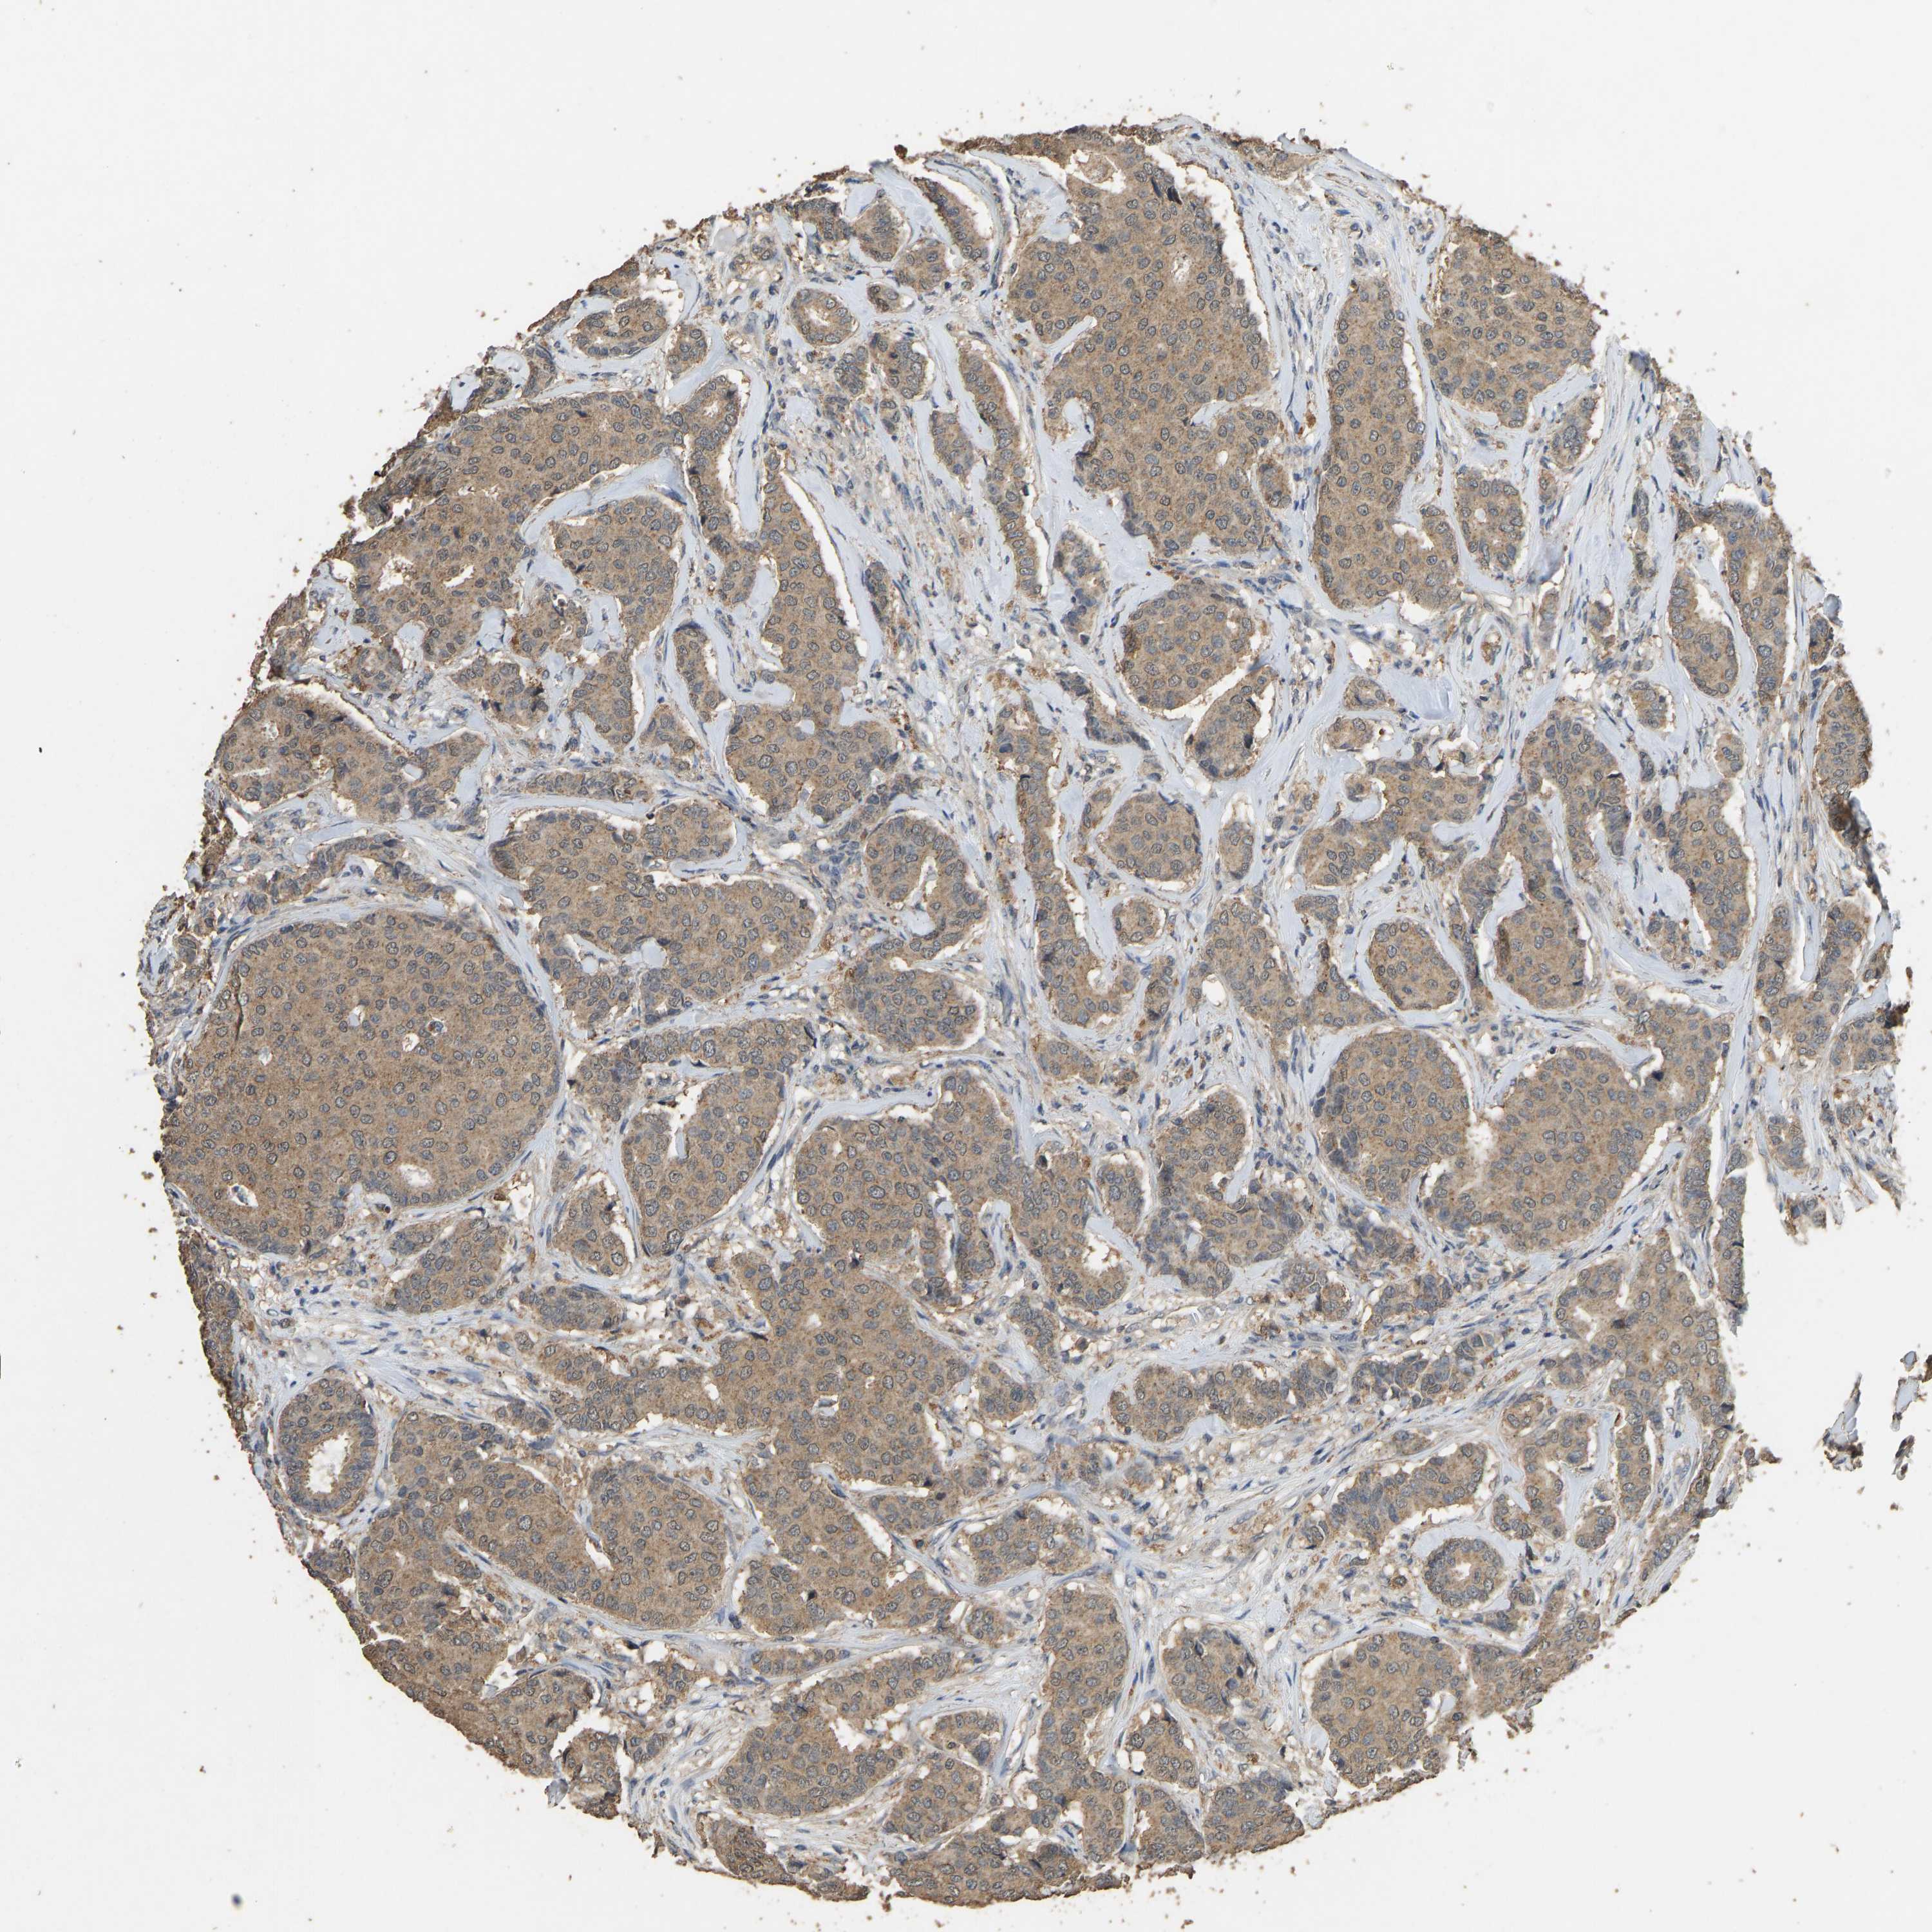

CANCER BREAST CANCER Show tissue menu

BRCA TCGA BRCA VALIDATION PROTEIN EXPRESSION